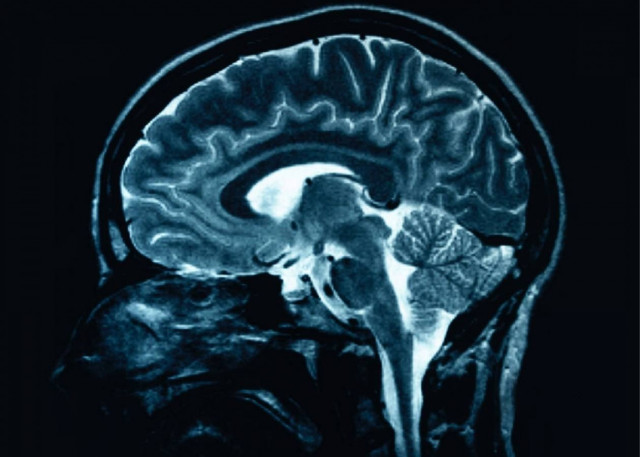

Σαφείς ενδείξεις για δομικές ανωμαλίες φέρουν οι εγκέφαλοι των ψυχοπαθών ανθρώπων, οι οποίοι έχουν καταδικαστεί για φόνο, βιασμό και άλλα βίαια εγκλήματα,

σύμφωνα με μία νέα βρετανική επιστημονική έρευνα, που δείχνει ότι η ψυχοπάθεια είναι τελικά μία διακριτή νευροαναπτυξιακή διαταραχή του εγκεφάλου.

Η νέα έρευνα έδειξε ότι οι ψυχοπαθείς, οι οποίοι χαρακτηρίζονται από έλλειψη ενσυναίσθησης για τους άλλους ανθρώπους, έχουν λιγότερη φαιά ουσία στις περιοχές εκείνες του εγκεφάλου που είναι σημαντικές για την κατανόηση των συναισθημάτων και των προθέσεων των άλλων.